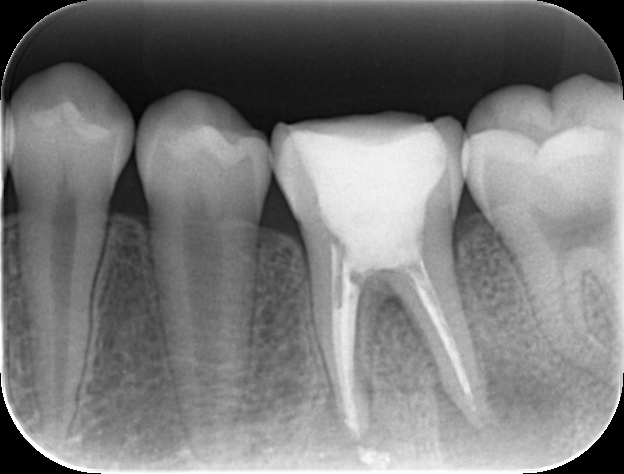

【術前の状態】 デンタルX線写真(後日掲載予定)を確認すると、左下6番(第1大臼歯)の近心および遠心に病変が見られました。 根管内には、しっかりと薬剤が充填されていない印象を受け、また根尖孔外には少量のMTAが漏出している状態でした。